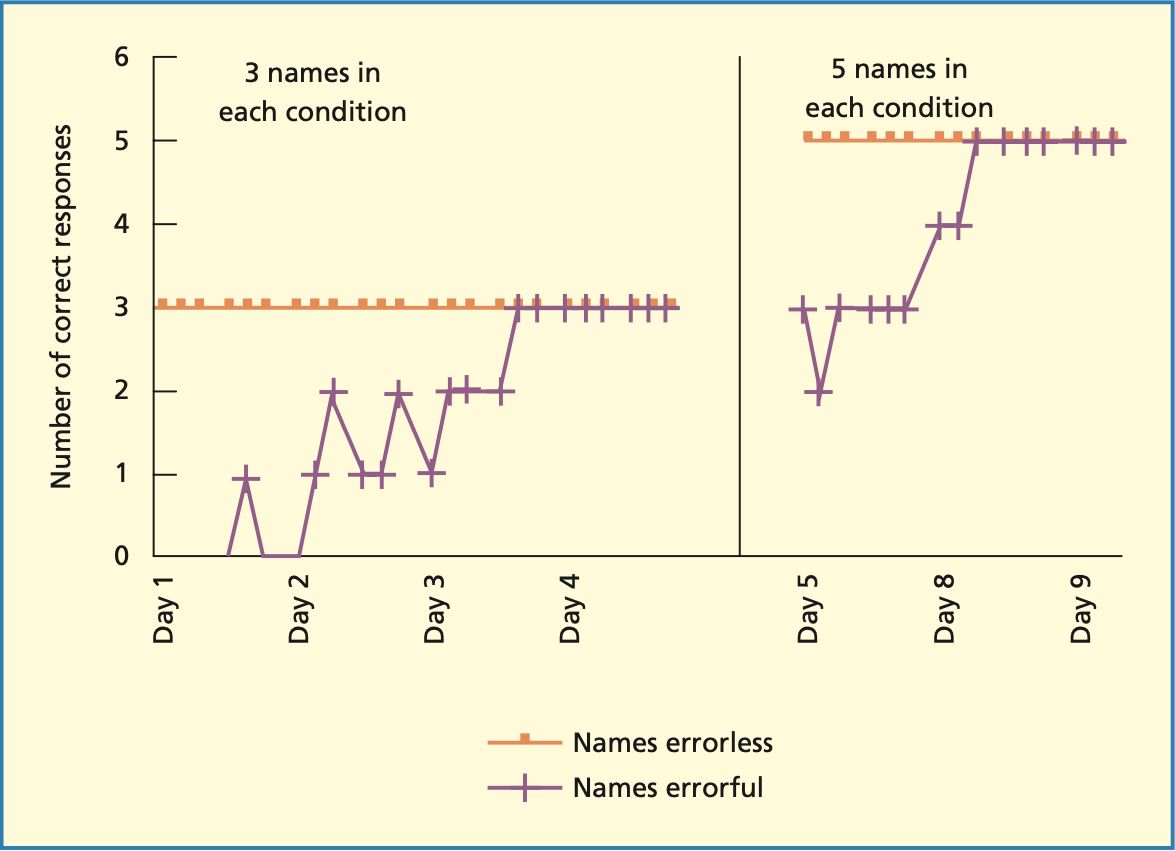

Lernen mit Amnesie